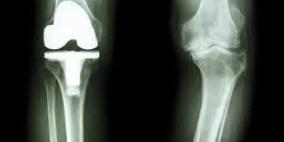

خشونة الركبة: أسبابها وطرق الوقاية والعلاج مع طبيب الأسرة د. سمير شماسنة